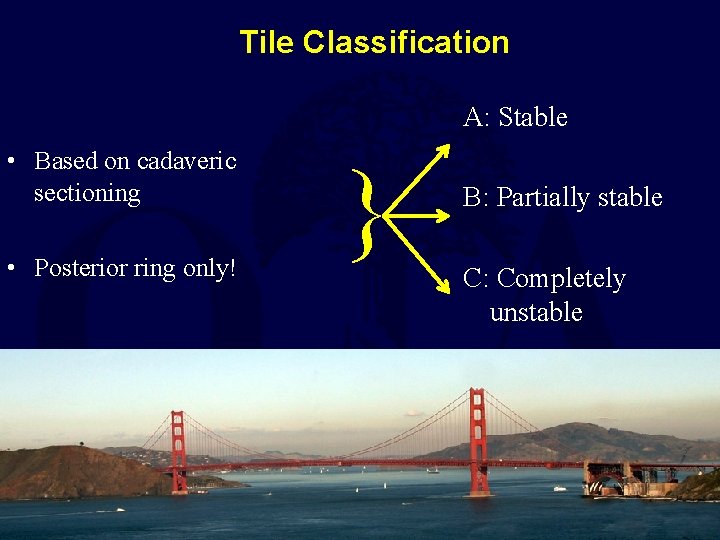

Tile Classification A: Stable • Based on cadaveric sectioning • Posterior ring only! } B: Partially stable C: Completely unstable